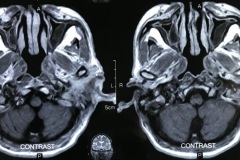

Scans